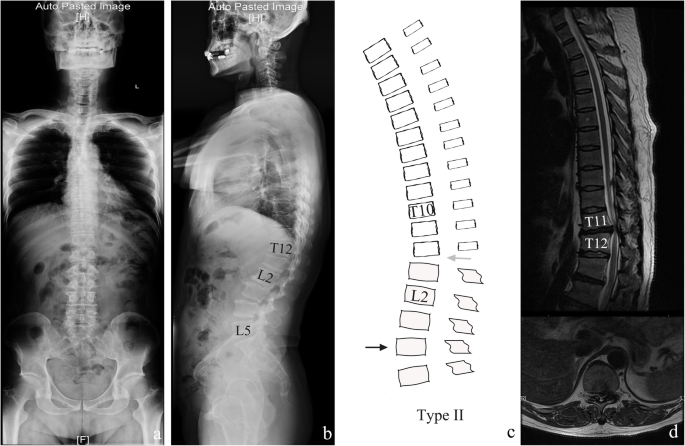

T11-t12 disc bulge symptoms-At T1112 there is a moderate posterior disc herniation which begins in the left paracentral position, but extruded disc material is seen extending caudally behind the T12 vertebra and Magnetic resonance imaging study showed a bulging disc and posterior osteophytes at T11T12 Results Surgical removal of the herniated disc and osteophytes rapidly

If the discs become displaced, or herniated, they can impinge on surrounding structures and cause uncomfortable symptoms The most commonly involved discs are the ones located between the Three of four patients with T11–T12 disc herniation experienced lower extremity weakness, and three patients had accentuated patellar tendon reflex Sensory disturbance was lt;p>You may not have any symptoms as probably most people who have disc bulges are completely asymptomatic But if you do, you may notice cirmuferential pain or